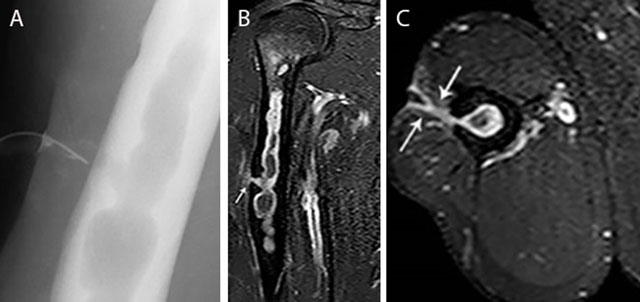

Figure 13

Chronic osteomyelitis of the right humerus with fistula formation. Plain radiograph (sinography) (a), coronal (b) and axial (c) Fat–Sat T1–WI after gadolinium contrast administration. The sinography (a) shows an intramedullary well defined lytic lesion with scalloping of the cortex. Note the presence of a catheter in the sinus. There is enhancement of the wall of the intra-osseous abscess and the wall of the fistula (white arrow) (b, c). Image courtesy Dr. H. Declercq, Dendermonde.

Inhomogeneous osteosclerosis and/or sequestrum formation (necrotic bone) is characteristic for chronic osteomyelitis on plain radiography. A sequestrum represents a segment of necrotic bone that is separated from the living bone by granulation tissue and bone resorption. It is typically denser than the living bone [13]. In some cases, a layer of new periosteal bone or involucrum is formed around the necrotic bone (Figures 7, 11, 12). On MRI, a sequestrum is hypo-intense on all pulse sequences. Gadolinium contrast administration may reveal a cloaca (opening in the involucrum) through which pus, granulation tissue and sequestra can be discharged. In addition, enhancement of sinus tracts tracking from the bone to the skin surface is well demonstrated on contrast enhanced MRI (Figure 13) [15].